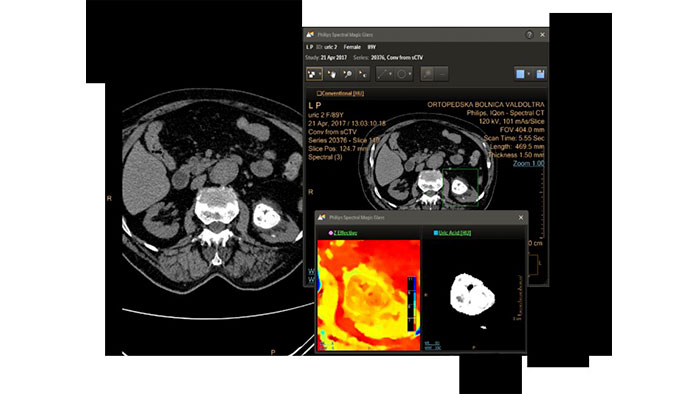

- Spectral Light Magic Glass

CT Spectral Light Magic Glass

Review spectral data in a range of not spectral-enhanced CT applications

Allows retrospective use of spectral data that was saved in a series of spectral base images (SBI).

The fast launch of LMG allows review and identification of the most relevant results to be launched into the application for further analysis.

Benefits

- The option is available from the following applications: Brain Perfusion, Functional CT, Liver Analysis, PAA, TAVI, Acute Multifunctional Review, Virtual Colonoscopy.

- Spectral Magic Glass can be launched only for CT images or images created on the Philips IQon Spectral CT.

- Spectral Magic Glass on PACS

CT Spectral Magic Glass on PACS*

IQon Spectral CT Functionality

IQon Spectral CT is the only scanner to offer CT Spectral Light Magic Glass and CT Spectral Magic Glass on PACS, helping radiologists review and analyze multiple layers of spectral data at once, including on their PACS.

Benefits

- On-demand simultaneous analysis of multiple spectral results for an Region Of Interest (ROI).

- Integrates into a health system’s current PACS setup for certain PACS vendors.

- Spectral results viewable, during a routine reading.

- Enterprise-wide spectral viewing and analysis allows access to capabilities virtually anywhere in the organization.